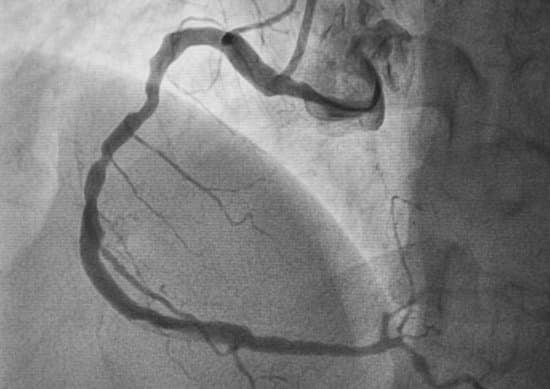

혈관 조영술:

조영제를 주입한 후 X선을 사용해 혈관의 내부 상태를 관찰하는 방법입니다.